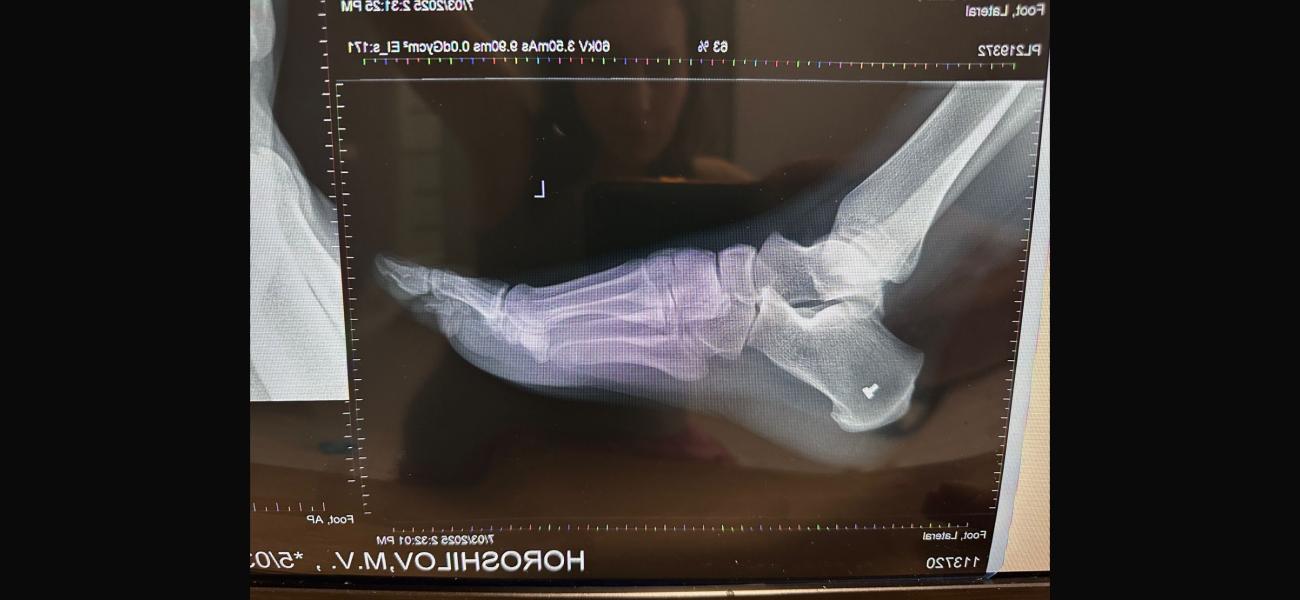

Ситуация следующая. Муж получил осколочное ранение, перелом плюсневой кости, осколок находиться в переломе прямо. Муж не чувствует 4х пальцев и не может шевелить ими. Хотя ранение было еще 22 января. К чему я, в госпитале усираются, что все само срастется и функционировать будет когда заживет, поэтому вынимать ничего не будут. Но как может срастись перелом, в котором осколок? В отпуске по ранению пытался лечь в госпиталь у нас в городе, до самого конца отпуска мурыжили что положат, ждите травматолога ( он бывает раз в сколько то дней, потому что по нескольким госпиталям бегает) когда мы наконец то 28го февраля попали к нему, он отказал в лечении. Сказал при части лечиться. Так вот хотелось бы услышать мнение врача. На случай если нам опять начнут говорить что все само пройдет.

П.с рентгены свои сделали, травматолога в частной не было в этот день, но сегодня сходим видимо просто в другую клинику, чтоб было на руках заключение. Но одно мнение специалиста хорошо, а два еще лучше